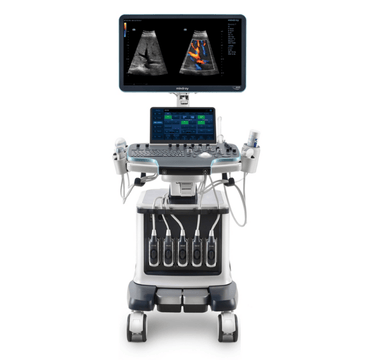

ZONE Sonography?

Technology

and the source of Mindray's "Living Technology"